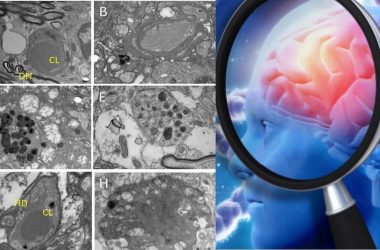

What Causes Alzheimer’s Disease? Scientists May Have Finally Discovered It

For years, scientists have been studying how the accumulation of toxic molecules in the brain could cause or contribute to Alzheimer's disease.